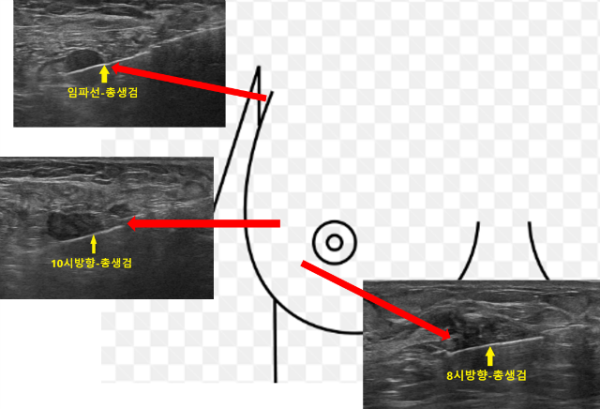

조직검사는 가장 유방암이 의심되는 부위인 오른쪽 8시방향 (2.4x2.7cm), 10시방향 (1.3x1.3cm), 그리고 겨드랑이 임파선, 총 3곳에서 하기로 하였습니다.

빠른 결과를 위해 응급으로 조직 검사를 의뢰하였고 3일만에 최종 결과가 나왔습니다.

예상했던대로 오른쪽 8시방향과 9시방향의 멍울들에서 모두 침윤성 유방암 (Invasive ductal carcinoma), 그리고 오른쪽 겨드랑이 임파선에서도 전이성 유방암 (Ductal carcinoma, metastatic) 으로 확인되었습니다.